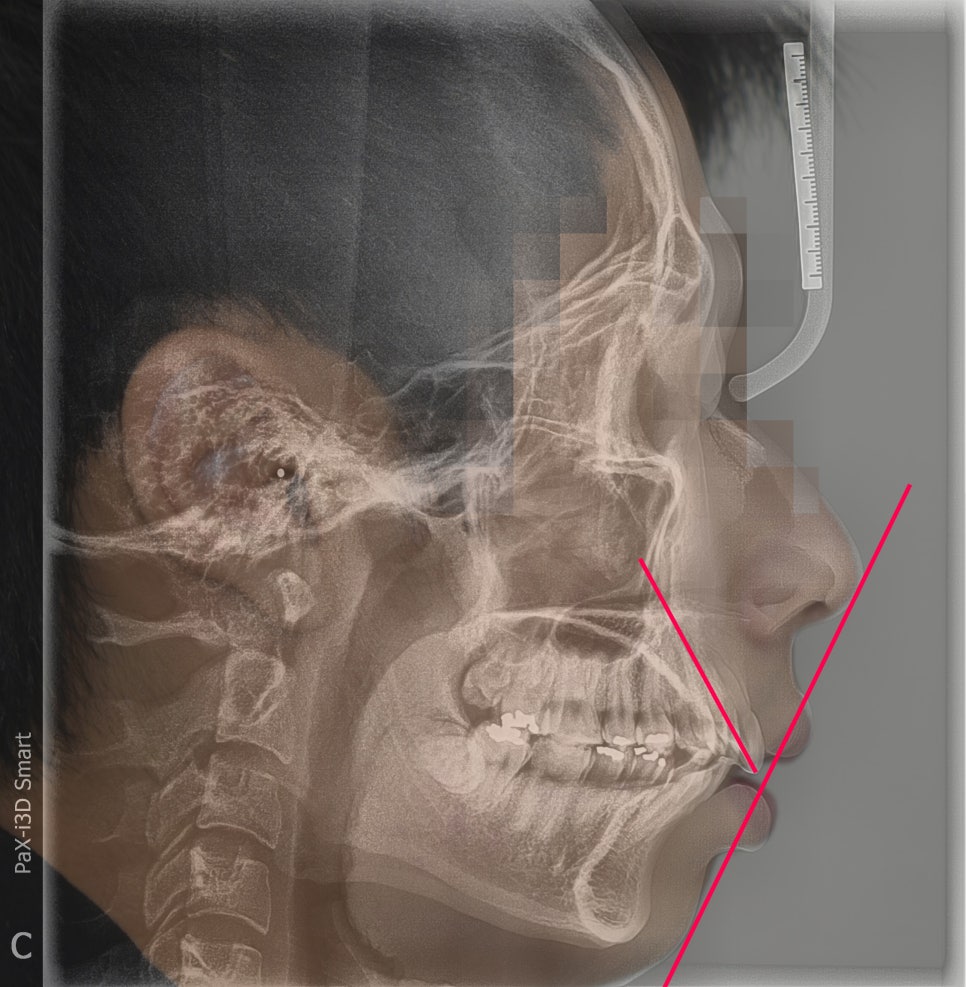

측면 사진 및 측면 두부방사선 사진을 중첩해서

보여드리는 사진입니다.

크게 2가지를 볼 수 있습니다.

- 심미선을 기준으로, 입술이 바깥쪽에 위치.

- 앞니의 치축이 앞쪽으로 많이 뻐드러져 있음.

근데, 이 분은 또 무턱의 경향이 살짝 느껴집니다.